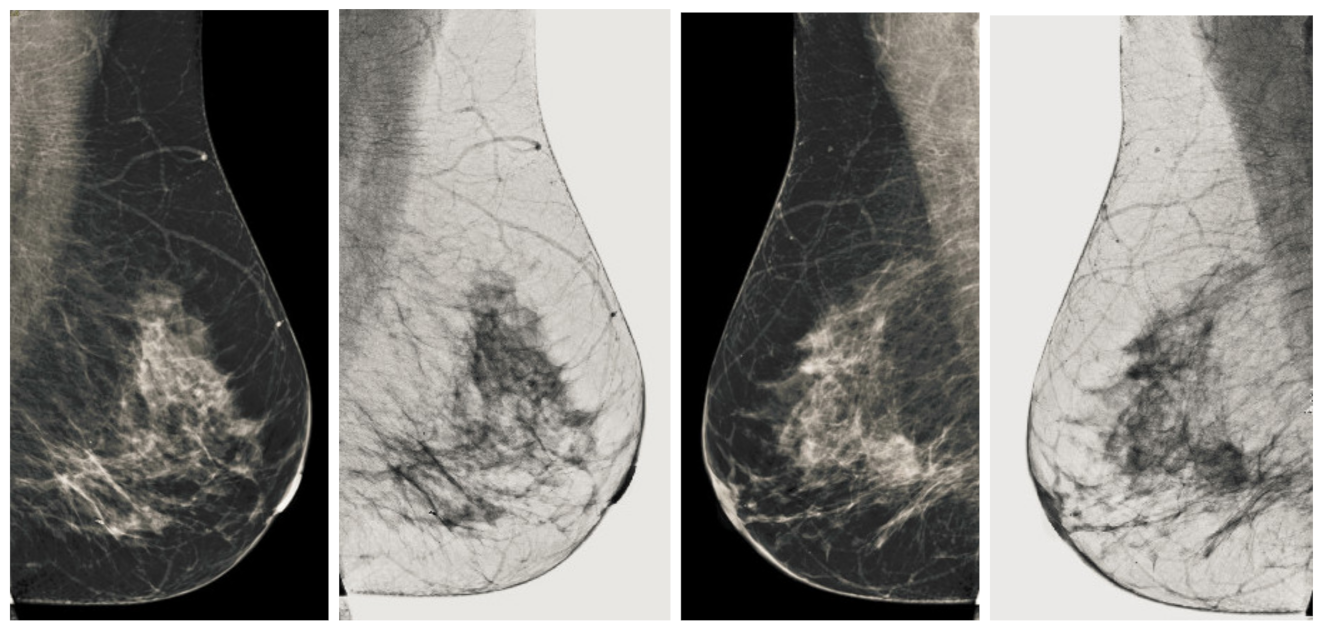

Figure 13.

Analysis of CC view of BI-RADS-4 mammogram images.

Figure 14.

Analysis of MLO view of BI-RADS-4 mammogram images.

We also measured the PSNR, the image contrast, and the EME of each category of databases, as we analyzed the image in terms of visual observation. The Table 3 shows the performance of our proposed image enhancement method. It can be seen from the Table 3 that our proposed method improved PSNR, contrast, and EME, and this also shows that our method can work on every category of BI-RADS. Because many techniques do not work on higher grade BI-RADS due to the complexity and the images are not of good quality. We obtained an average improvement in PSNR, contrast, and EME in the Table 4. For more observations, we analyzed the visual image of each category and we analyzed the CC and MLO of each category as shown in the Figure 7, Figure 8, Figure 9, Figure 10, Figure 11, Figure 12, Figure 13, Figure 14, Figure 15 and Figure 16. From the figures, every detail of image of every category can be observed, leading to better segmentation of the abnormal region. This image enhancement technique can be used as preprocessing steps for the detection of breast cancer. It is a very fast processing algorithm and it takes on 21.13 s. It gives opportunity to medical experts to analyze the mammogram images very quickly to propose the timely treatment.